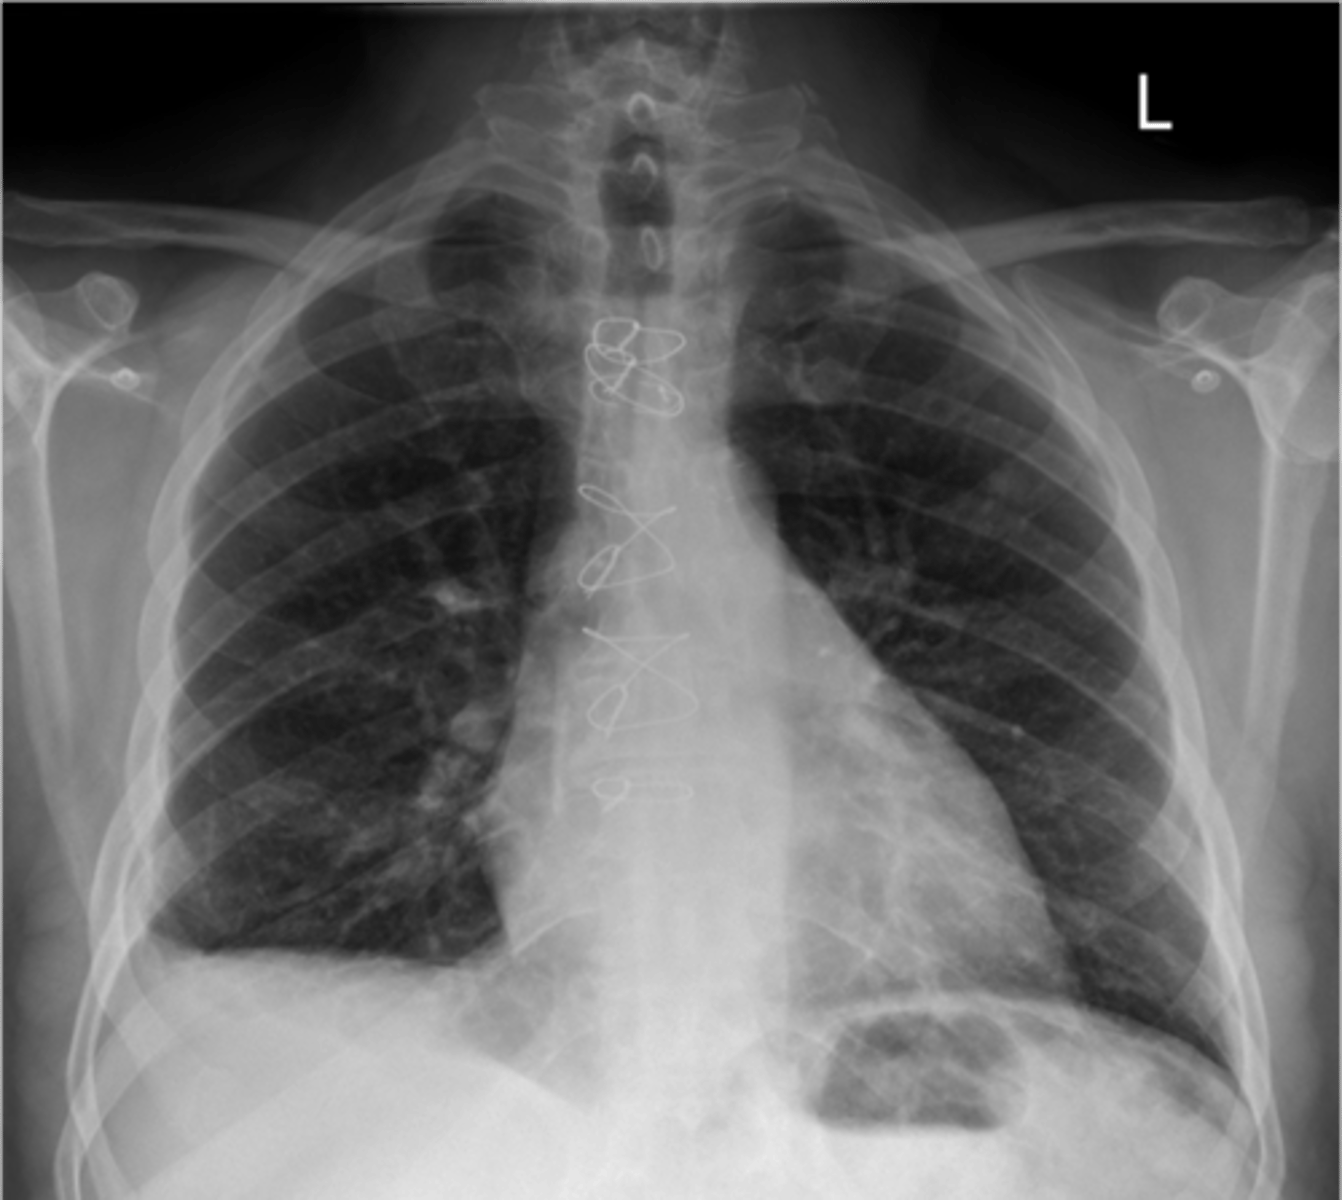

congestive heart failure

knowt flashcard image